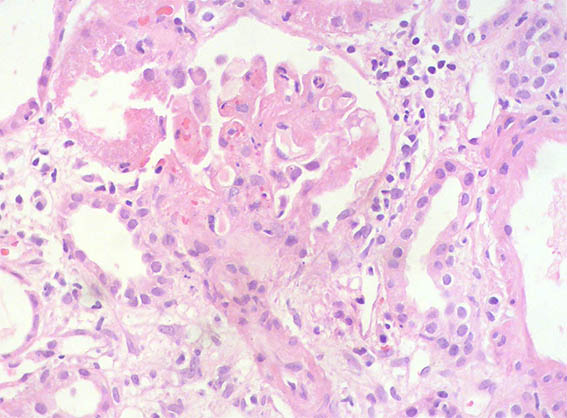

A 25-year-old woman with no relevant history is evaluated for presenting 3 months of evolution of constitutional symptoms, disseminated skin lesions with vasculitis-like appearance, polyarthritis affecting small and medium joints, anemia, acute phase reactants elevation, lymphopenia, hypocomplementemia C3 and C4, uroanalysis with active sediment and subnephrotic proteinuria: 1.8 g/24h; Cr; 1.1 mg/dL, BUN: 18 mg/dL. ANAs and anti-DNA positive at high titers, anti-RNP positive, VDRL falsely positive. Anticardiolipin and lupus anticoagulant: negative, other markers for APS: Negative.

See the images of the renal biopsy.

Figure 6. H&E, X400.

What lesion is evidenced in figures 6, 7 and 8 and what is its etiology?